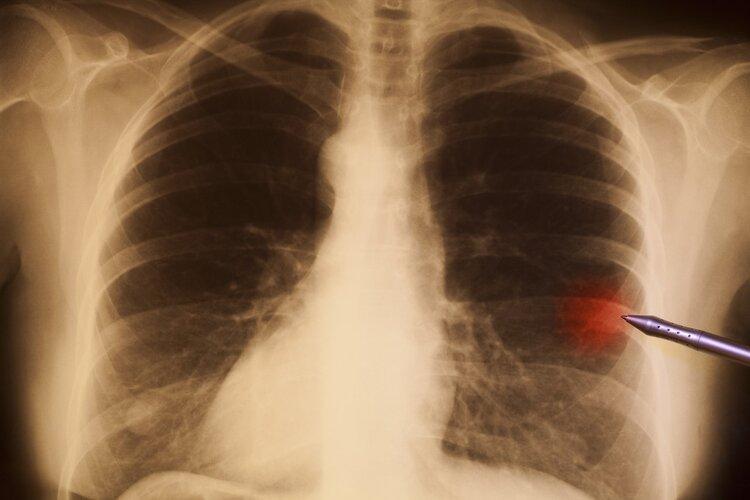

原來近段時間以來,劉女士總是胸痛、咯血,實在難以忍受便到了醫院就診,結果被癌症肺癌。這讓煙酒不沾的她一時無法接受,擔心是誤診,醫生解釋劉女士的肺癌可能與被動吸入二手菸、長期情緒不佳等因素有關。

其實,吸菸和不吸菸患上的肺癌類型並不一樣。福建省腫瘤醫院腫瘤內科主任醫師林根介紹:肺癌可以分爲小細胞肺癌非小細胞肺癌兩類,其中非小細胞肺癌在肺癌中佔比75%—85%。90%的小細胞癌患者是菸民,肺腺癌患者中不吸菸的人很多,而且近三十年來女性肺癌患者越來越多。